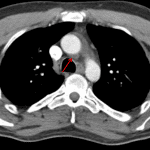

- Chest

- Mild dependent atelectasis/scarring in both lower lobes and the lingula

- Low density mediastinal fluid extending to the inferior margin of the aortic arch, consistent with fluid within the superior aortic recess of the transverse sinus

Diagnosis

- High-riding pericardium (anatomic variant)

High-riding pericardium (anatomic variant) without evidence of traumatic aortic injury.

Soft tissue laceration/contusion along the anterior upper left chest and neck.